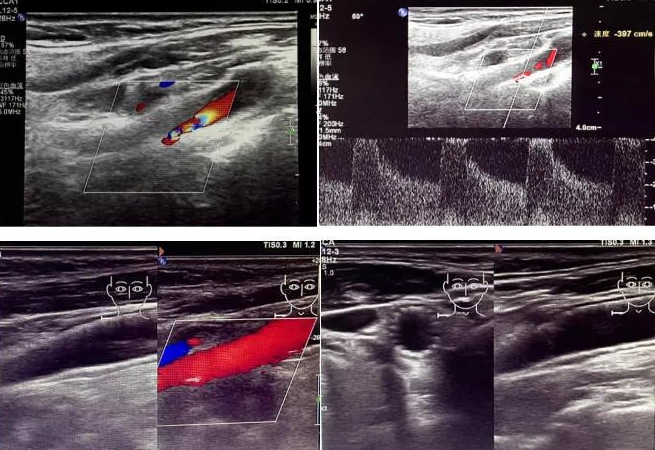

該患者因反復(fù)頭暈前來國文醫(yī)院就診。經(jīng)醫(yī)院超聲科運用高端超聲設(shè)備進行頸動脈超聲檢查后發(fā)現(xiàn),其右側(cè)頸動脈狹窄程度超過 90%。如此嚴重的狹窄狀況,猶如高速公路上的嚴重堵車,使得血液流通受阻,大大增加了腦梗死的風(fēng)險,時刻威脅著患者的生命安全。

頸動脈超聲檢查作為一種無創(chuàng)、安全且準確的篩查手段,在評估血管健康狀況方面發(fā)揮著重要作用。它能夠清晰地顯示血管的狹窄程度以及斑塊性質(zhì),為臨床診療提供可靠的依據(jù)。國文醫(yī)院超聲科配備的高端超聲設(shè)備,更為精準診斷提供了有力支持。